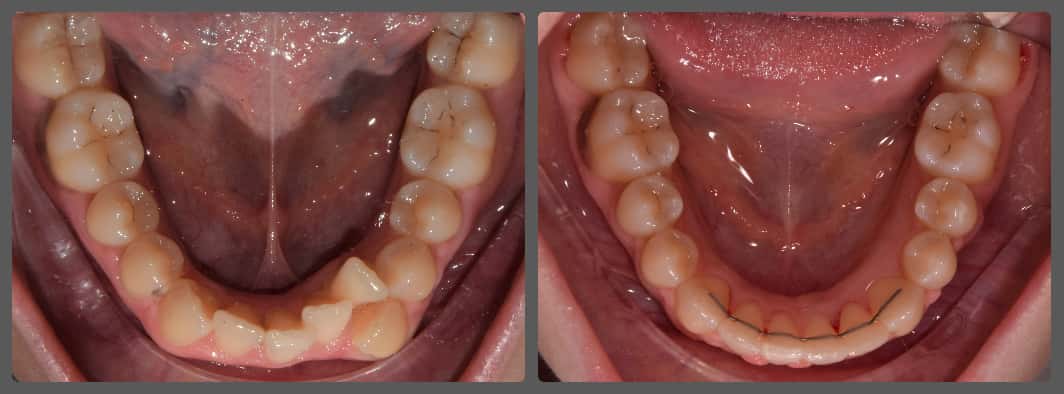

Balázs súlyos alsó torlódása miatt keresett fel magánrendelésemen. A diagnosztikus vizsgálatok során előbbin túl alsó-felső fogívszűkületet, valamint nyitott harapási hajlamot állapítottam meg. Kezelését Pitts21 alsó-felső rögzített fogszabályozó készülékkel kezdtük meg. A nyitott harapási hajlamot a hátsó fogakra helyezett harapásemelővel kontrolláltuk. A torlódott fogaknak tolórugóval és interproximális redukcióval teremtettünk helyet, és intermaxilláris gumihúzással tökéletesítettük a harapást. A fogszabályzó kezelés teljes időtartama alatt Balázs 110%-osan együttműködő volt, ezért 21 hónap alatt sikerült kiemelkedő végeredményt elérnünk.